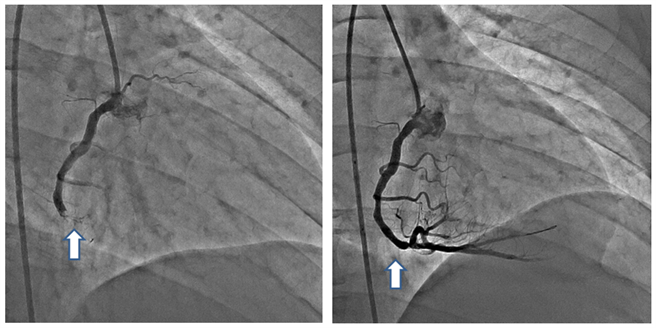

患者经心导管发现(左图)右冠状动脉因血栓形成,导致完全堵塞,引发心肌梗塞。(右图)经置放心血管支架,右冠状动脉重获血液循环。(澄清医院提供/冯惠宜台中传真)

该名男子正中午开着货车亲赴急诊,经心电图、X光、心臟超音波等检查,会诊心臟内科,诊断为急性心肌梗塞发作,其右冠状动脉因血栓形成导致完全堵塞,立刻进行紧急心导管手术。澄清医院心臟内科医师孙德光表示,经进行血栓抽吸术、气球扩张术及支架置入术后,打通完全堵塞的右冠状动脉,于90分钟内重获血液顺畅循环。